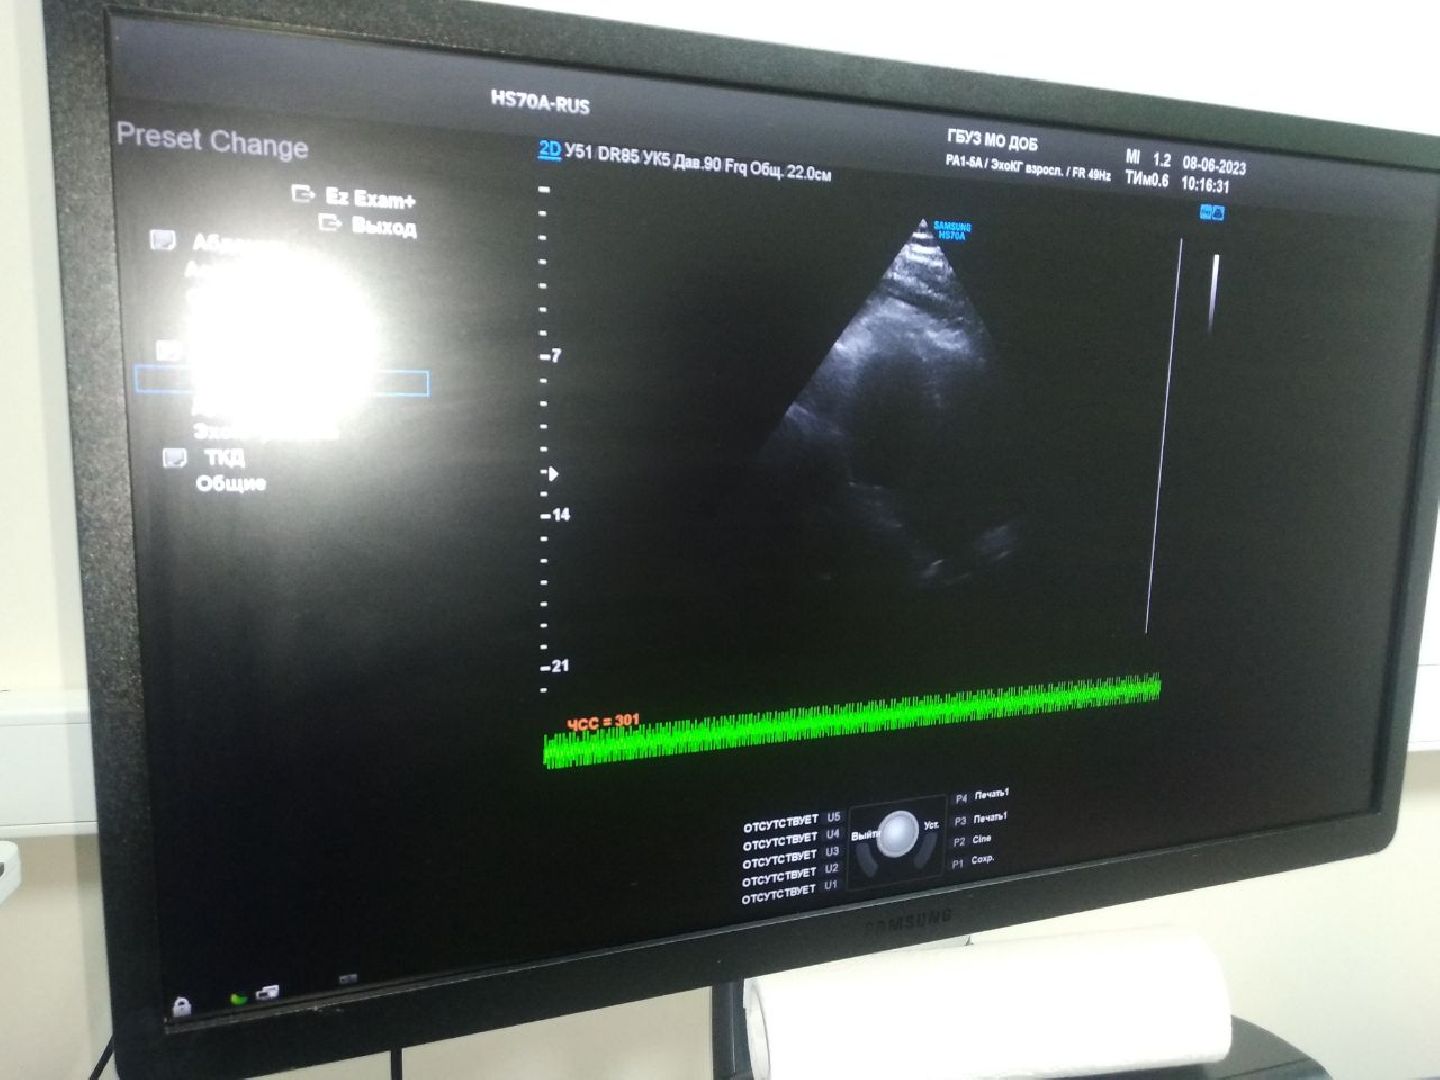

«Я — специалист самого широкого профиля. Могу проводить ультразвуковую диагностику как взрослых, так и детей, исследование почек, сердца или печени, и пренатальную диагностику. Самое главное, чтобы было качественное медицинское оборудование. К счастью, в Дмитровской областной больнице самые современные аппараты УЗИ», — рассказала Попова.